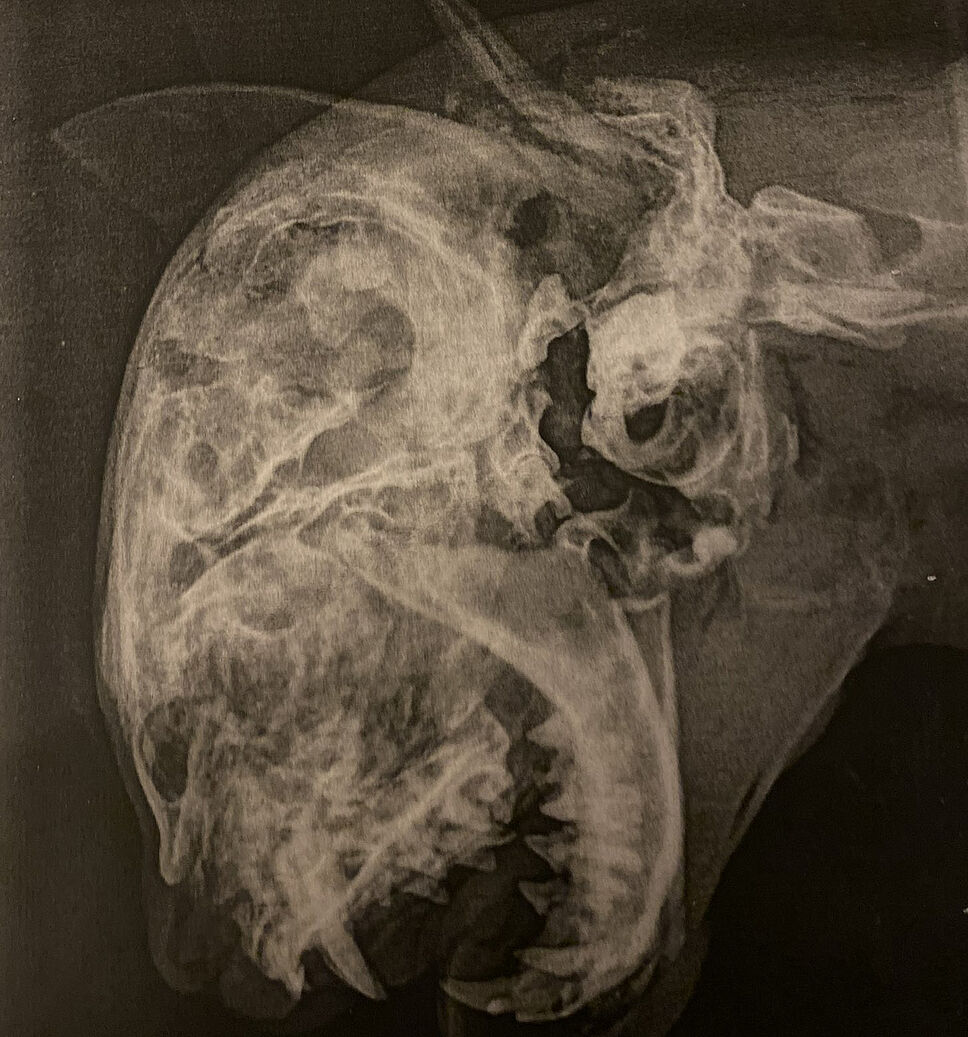

Des factures multiples ayant entraîné la mort

Un acte d’une barbarie inouïe : le rapport d’autopsie a constaté un hématome crânien, de multiples fractures des os du crâne, une fracture cervicale ainsi qu’un « œil gauche percé et vidé ». Toutes ces lésions résultent d’une « action volontaire de causer la mort en écrasant la tête de l’animal contre le sol (…) avec le pied, une masse, un marteau ou un autre objet lourd ».